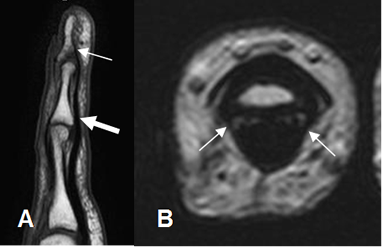

Fig 30. Mecanismo flexor normal.

A: RM sagital en T1. Inserción del flexor superficial en la base de la falange media (Flecha gruesa) y del flexor profundo, en la base de la falange distal (Flecha delgada).

B: RM axial en T2. Mecanismo flexor, fijado por las poleas en las falanges.